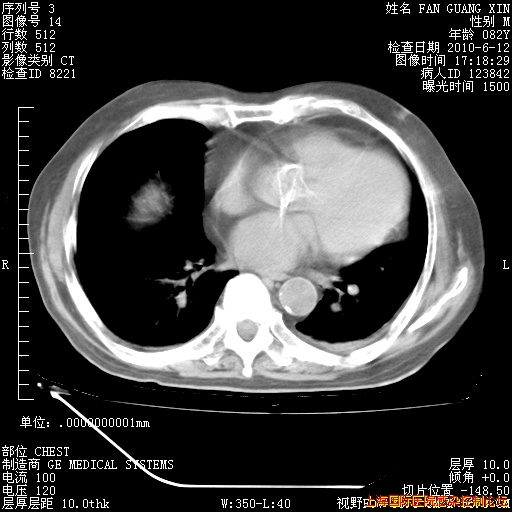

补发6月12日肺部CT肺窗

6月12日肺窗